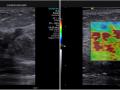

Tag: mastologia

Bases físicas da mamografia